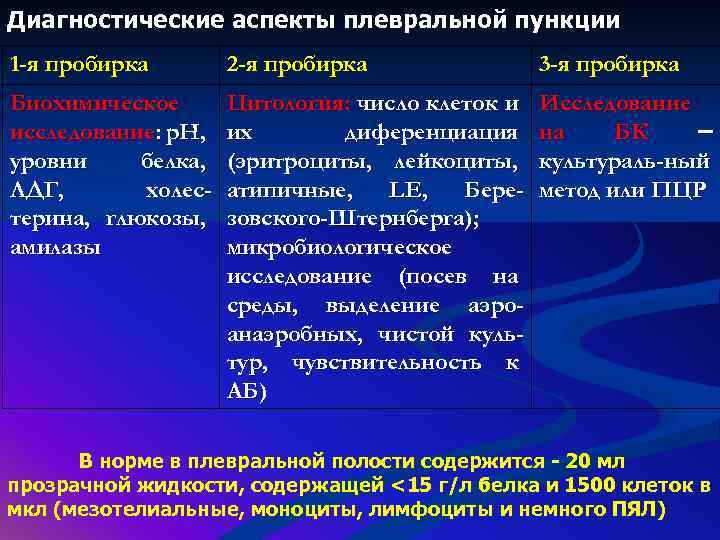

Диагностика плеврального выпота: что нужно знать